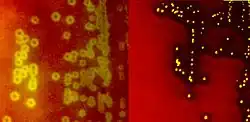

Species of streptococci are classified based on their hemolytic properties.[10] Alpha-hemolytic species cause oxidization of iron in hemoglobin molecules within red blood cells, giving it a greenish color on blood agar. Beta-hemolytic species cause complete rupture of red blood cells. On blood agar, this appears as wide areas clear of blood cells surrounding bacterial colonies. Gamma-hemolytic species cause no hemolysis.[11]

When alpha-hemolysis (α-hemolysis) is present, a blood based agar under the colony will appear dark and greenish due to the conversion of hemoglobin to green biliverdin. Streptococcus pneumoniae and a group of oral streptococci (Streptococcus viridans or viridans streptococci) display alpha-hemolysis. Alpha-hemolysis is also termed incomplete hemolysis or partial hemolysis because the cell membranes of the red blood cells are left intact. This is also sometimes called green hemolysis because of the color change in the agar.

Beta-hemolysis (β-hemolysis), sometimes called complete hemolysis, is a complete lysis of red cells in the media around and under the colonies: the area appears lightened (yellow) and transparent. Streptolysin, an exotoxin, is the enzyme produced by the bacteria which causes the complete lysis of red blood cells. There are two types of streptolysin: Streptolysin O (SLO) and streptolysin S (SLS). Streptolysin O is an oxygen-sensitive cytotoxin, secreted by most group A Streptococcus (GAS), and interacts with cholesterol in the membrane of eukaryotic cells (mainly red and white blood cells, macrophages, and platelets), and usually results in beta-hemolysis under the surface of blood agar. Streptolysin S is an oxygen-stable cytotoxin also produced by most GAS strains which results in clearing on the surface of blood agar. SLS affects immune cells, including polymorphonuclear leukocytes and lymphocytes, and is thought to prevent the host immune system from clearing infection. Streptococcus pyogenes, or GAS, displays beta hemolysis.

Alpha-hemolytic S. viridans (right) and beta-hemolytic S. pyogenes (left) streptococci growing on blood agar